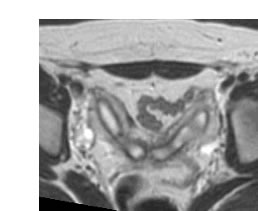

HYSTER SERIES/Uterusdi1.gif

Previous | HysterGallery | Next